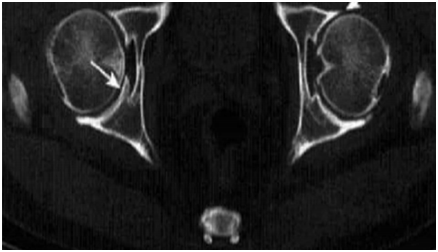

骨关节炎 (osteoarthritis.OA)是关节软骨的退变和继发性骨质增生的一种慢性关节疾病,又可称为骨关节痛、骨关节病、老年性关节炎、增生性关节炎、萎缩性关节炎、肥大性关节炎、软骨软化性关节炎节病等。多见于中老年人,其发病率与年龄增长呈正相关。全世界范围内估计,60 岁以上的 9.6%的男性和 18.0%的女性有骨性关节炎症状。并且骨性关节炎主要影响承重关节。骨关节炎主要有两大临床特征,分别是退化以及增生。退化包括了关节软骨纤维化和退化,韧带松弛,关节周围肌肉萎缩等;增生则包括了骨赘形成、软骨下骨硬化、滑膜组织增生、关节囊增生等。骨关节炎的治疗目的是缓解疼痛,延缓关节软骨退变,改善生活质量。在治疗过程中,临床医生常使用非甾体消炎药、氨基葡萄糖等药物。